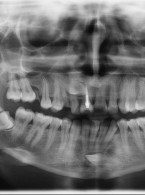

Pokrycie mnogich recesji dziąsłowych

metodą płata przesuniętego dokoronowo z wykorzystaniem przeszczepu podnabłonkowej tkanki łącznej i kolagenowego materiału ksenogennego po wcześniejszej rekonstrukcji połączenia szkliwno-cementowego - opis przypadku